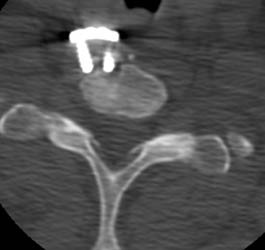

This axial CT taken at the same time shows to

better advantage how the distal screws are fully out of the ventral cortex of C7

on the right hand distal screw and only 1 thread of the left hand distal screw

remains in the bone itself. The fixation plate is also 1cm ventral to the body

of C7 at this level.